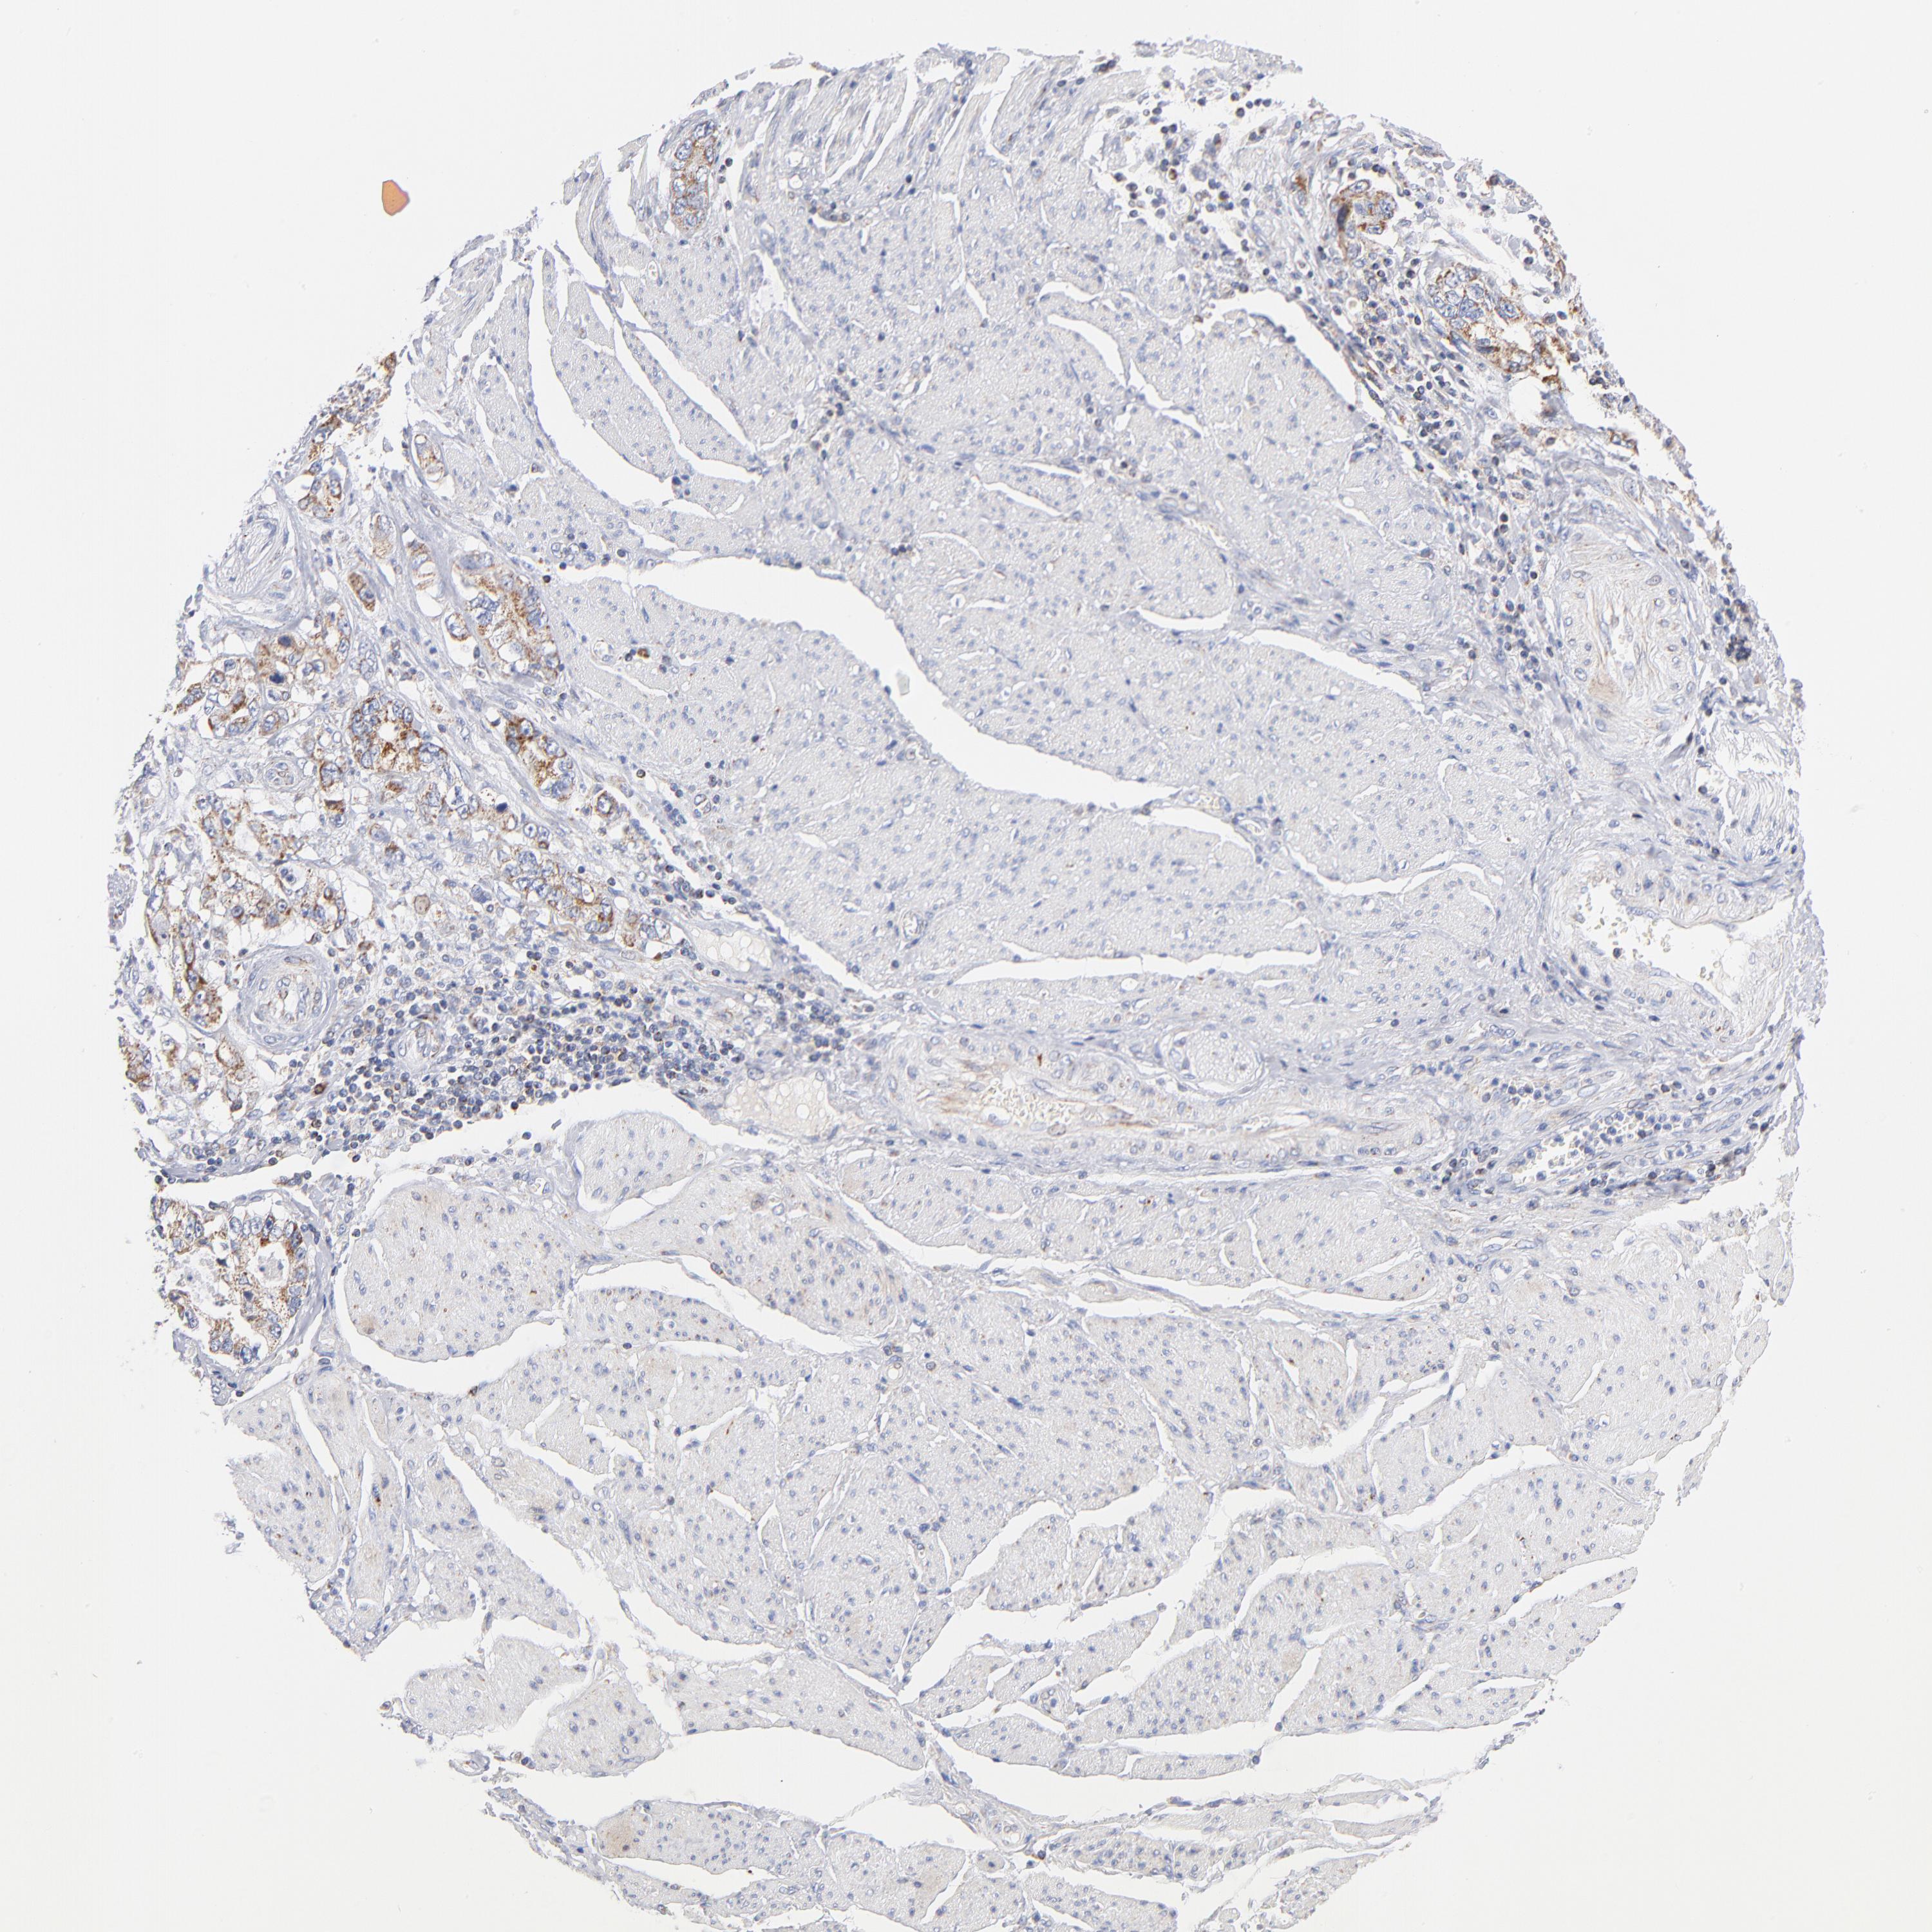

STOMACH CANCER - Protein expressioni

A mouse-over function shows sample information and annotation data. Click on an image to view it in a full screen mode. Samples can be filtered based on level of antibody staining by selecting one or several of the following categories: high, medium, low and not detected. The assay and annotation is described here.

Antibody stainingi

Antibody staining in the annotated cell types in the current human tissue is reported as not detected, low, medium, or high, based on conventional immunohistochemistry profiling in selected tissues. This score is based on the combination of the staining intensity and fraction of stained cells.

Each image is clickable and will lead to virtual microscopy that enables deeper exploration of all samples and also displays staining intensity scores, fraction scores and subcellular localization as well as patient and tissue information for each sample.

Antibody HPA040786

Antibody CAB003782

Staining

High

Medium

Low

Not detected

Intensity

Strong

Moderate

Weak

Negative

Quantity

>75%

75%-25%

<25%

None

Location

Nuclear

Cytoplasmic/membranous

Cytoplasmic/membranous,nuclear

Adenocarcinoma, NOS